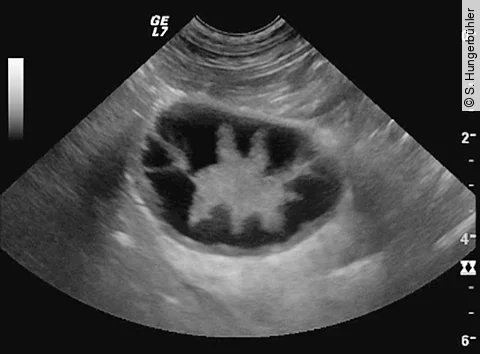

Die Mukozele der Gallenblase ist eine immer häufiger diagnostizierte Erkrankung, die mit lebensbedrohlichen Komplikationen einhergehen kann. Die sonografische Untersuchung ist wichtigster Bestandteil der Diagnostik.